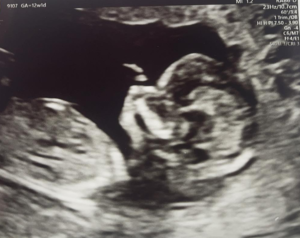

MOJA PORODNA ZGODBA – 1. DEL

Doma se že nekaj časa crkljamo z našo štručko, danes pa sem si končno utrgala malo časa, da spišem svojo...